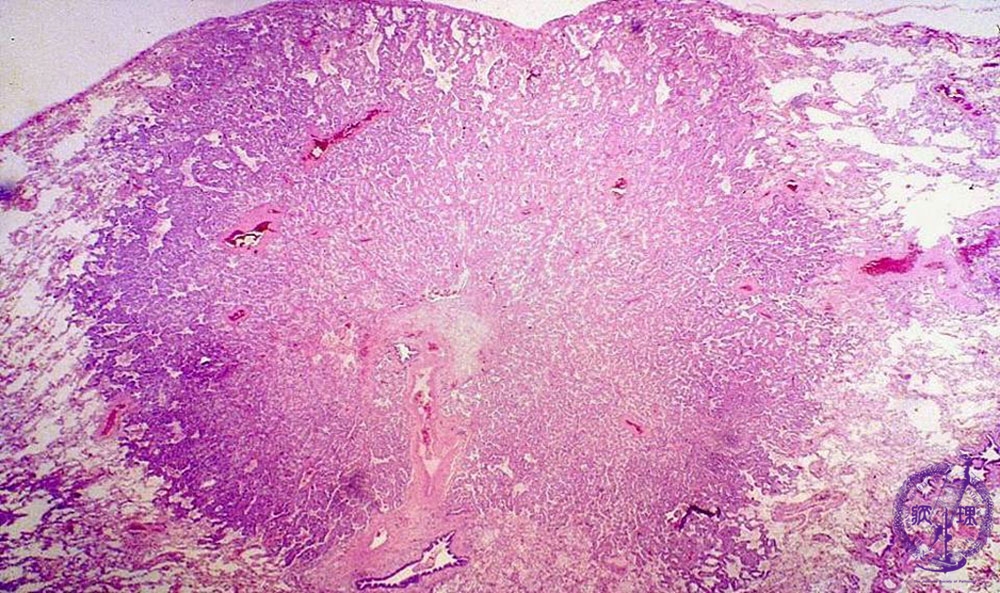

非小細胞肺癌(腺癌)ミクロ像(HE弱拡大)

ミクロ像(HE弱拡大):小型の腺癌では比較的均一な組織像を示す。腺癌が大型化するにつれ様々な組織型が混在してくる傾向にある。